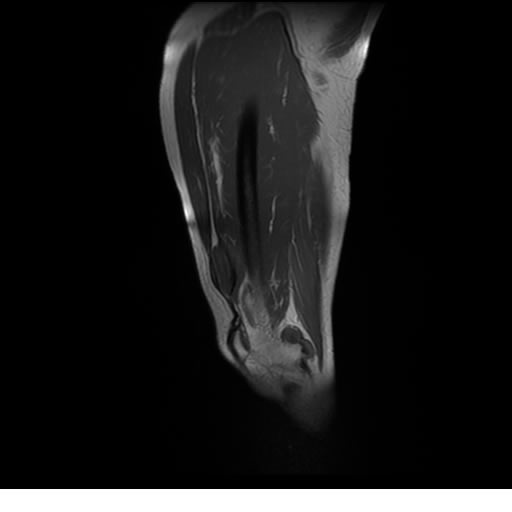

Se realiza estudio de MRI de pierna izquierda, utilizando secuencias Spin Echo y GRE en diferentes planos, se realiza angio MRI en fase arterial y venosa de pierna izquierda

El estudio demuestra masa a nivel de los músculos gemelos, más evidente en secuencia con pulso de saturación de grasa, en el estudio de angio resonancia de pierna la fase arterial no muestra ninguna anormalidad, en la fase venosa se observa acumulo del medio de contraste a este nivel.

Se concluye que se observa una masa de tejido muscular sumamente vascularizada compatible con un hemangioarcoma.